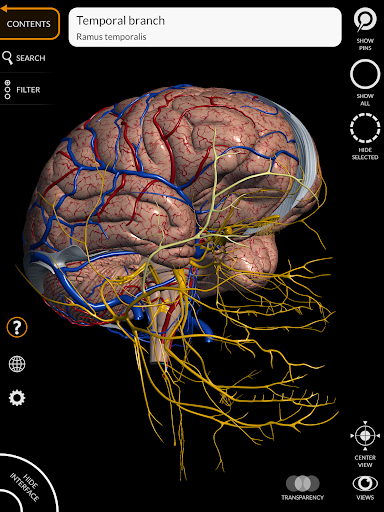

"Anatomía - Atlas 3D" permite estudiar la anatomía humana de forma fácil e interactiva.

A través de una interfaz sencilla e intuitiva es posible observar cada estructura anatómica desde cualquier ángulo.

Los modelos anatómicos 3D son especialmente detallados y con texturas de hasta una resolución de 4k.

La subdivisión por regiones y las vistas predefinidas facilitan la observación y el estudio de partes individuales o grupos de sistemas y las relaciones entre los diferentes órganos.

MODELOS ANATÓMICOS 3D

• Sistema cardiovascular • Sistema

nervioso • Sistema respiratorio • Sistema digestivo • Sistema urogenital (masculino y femenino) • Sistema endocrino • Sistema linfático • Sistema ocular y auditivo CARACTERÍSTICAS • Interfaz sencilla e intuitiva • Rotar y hacer zoom en cada modelo en el espacio 3D • Opción para ocultar o aislar uno o varios modelos seleccionados • Filtro para ocultar o mostrar cada sistema • Función de búsqueda para encontrar fácilmente cada parte anatómica • Función de marcador para guardar vistas personalizadas • Rotación inteligente que mueve el centro de rotación automáticamente • Función de transparencia • Visualización de músculos a través de niveles de capas desde las superficiales hasta las más profundas • Al seleccionar un modelo o un pin, aparece el término anatómico relacionado • Descripción de los músculos: origen, inserción, inervación y acción • Mostrar/ocultar interfaz de usuario (muy útil con pantallas pequeñas) MULTILINGÜE • Los términos anatómicos y la interfaz de usuario están disponibles en 11 idiomas: latín, inglés, francés, alemán, italiano, portugués, turco, ruso, español, Chino, japonés y coreano • Los términos anatómicos se pueden mostrar en dos idiomas simultáneamente REQUISITOS DEL SISTEMA • Android 8.0 o posterior, dispositivos con al menos 3 GB de RAM Reversi